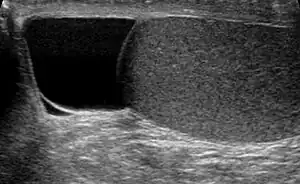

| Ultrasound of a testicle (grey) and a spermatocele (black). | |